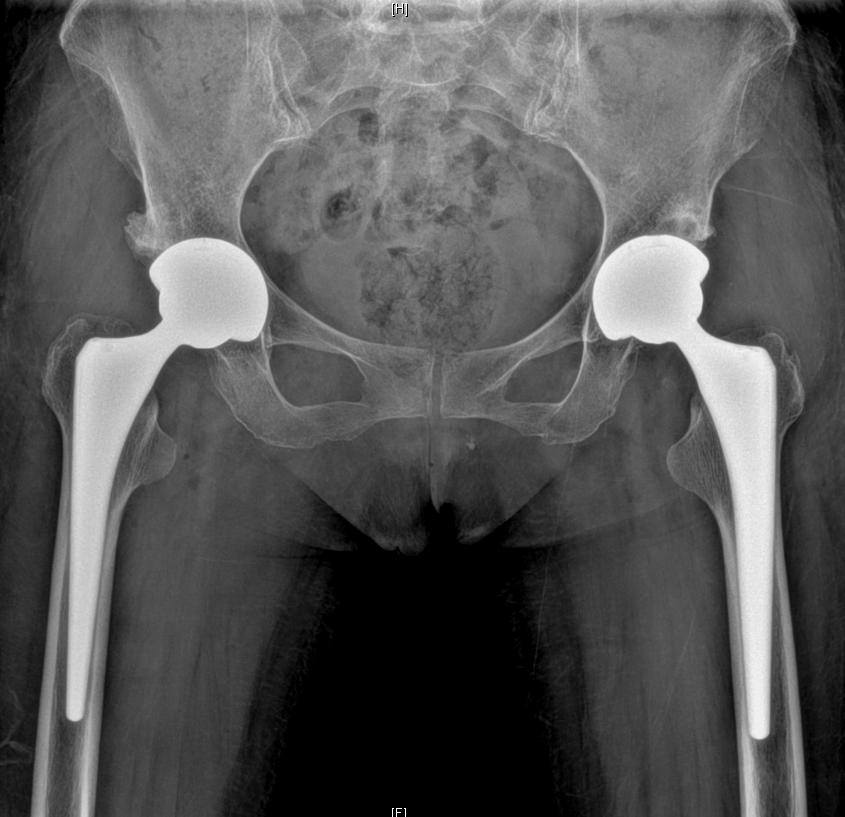

인공 고관절의 부품 구성

인공 고관절 치환술에서 사용되는 인공 관절은 여러 부품으로 구성되어 있으며, 각 부품은 고관절의 기능을 모방하고, 환자의 관절을 대체하는 역할을 합니다. 인공 고관절의 주요 부품들을 살펴보겠습니다.

소켓(컵) 부분

골반의 고관절 소켓을 대체합니다.

보통 금속, 세라믹, 플라스틱 등의 재료로 만들어집니다.

볼(헤드) 부분

대퇴골의 머리를 대체하는 부분입니다.

금속, 세라믹 또는 합금으로 제작됩니다.

대퇴골 줄기(스템) 부분

대퇴골 내부에 삽입되어 고정되는 부분입니다.

주로 금속 재료로 만들어지며, 대퇴골과 통합되도록 설계됩니다.

라이너 부분

볼과 소켓 사이에 위치하여 마찰을 줄이고 부드러운 움직임을 가능하게 합니다.

대개 폴리에틸렌과 같은 플라스틱 재료로 제작됩니다.